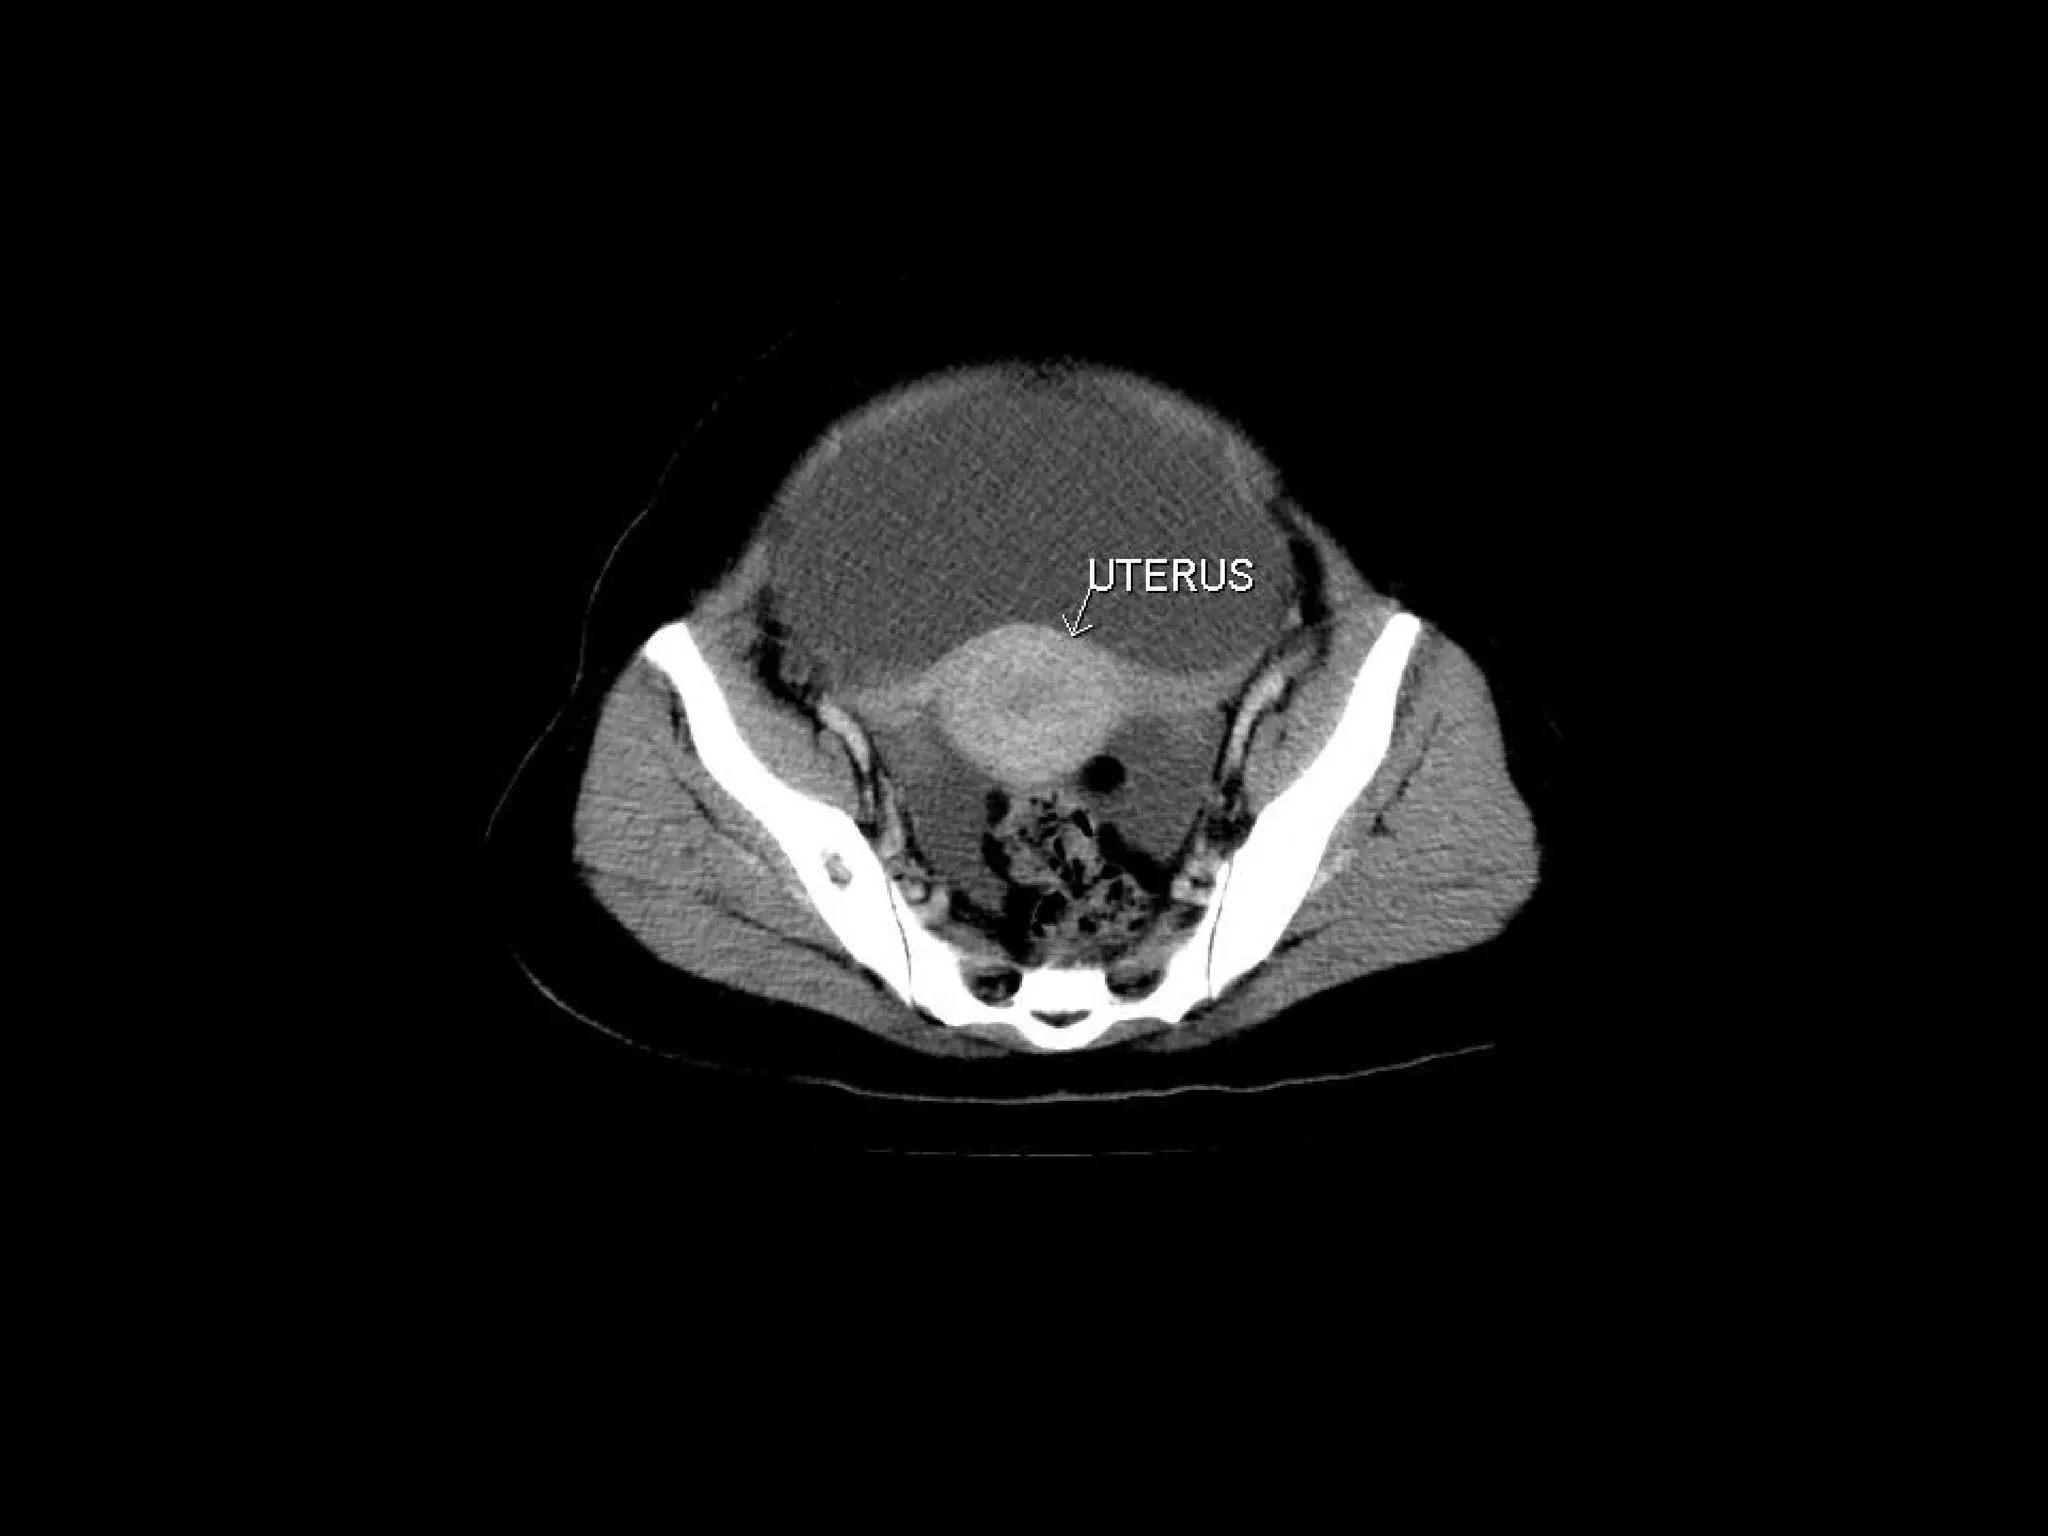

Radiographers are medical professionals who perform diagnostic imaging examinations and procedures to help physicians diagnose and treat diseases. They work under the supervision of radiologists to operate X-ray, CT, MRI, ultrasound and other medical imaging equipment and must have a strong understanding of human anatomy and pathology. Radiographers are responsible for correctly positioning patients, ensuring proper imaging techniques are used, and evaluating the quality of the resulting images.